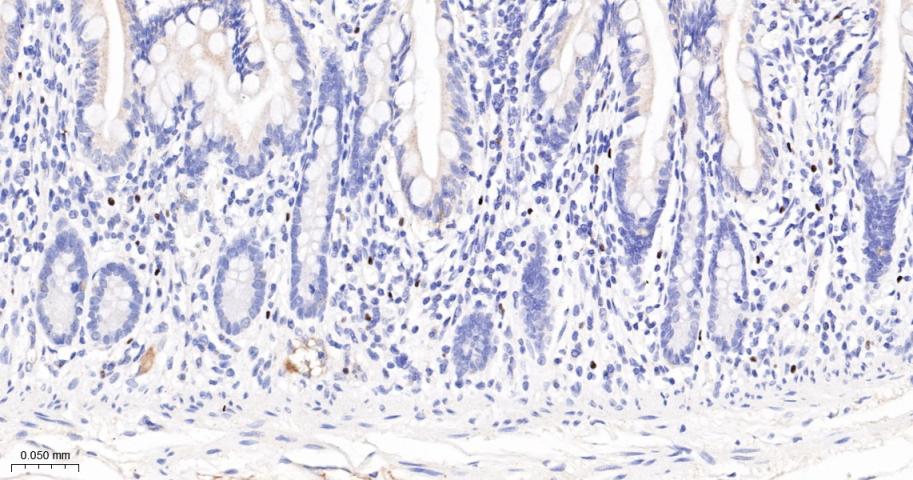

Paraformaldehyde-fixed, paraffin embedded Human Small Intestine; Antigen retrieval by boiling in sodium citrate buffer (pH6.0) for 15 min; The section was incubated with GATA2/3 Monoclonal Antibody, Unconjugated (bsm-61203R) at 1:200 overnight at 4°C, followed by conjugation to the bs-0295G-HRP and DAB (C-0010) staining.